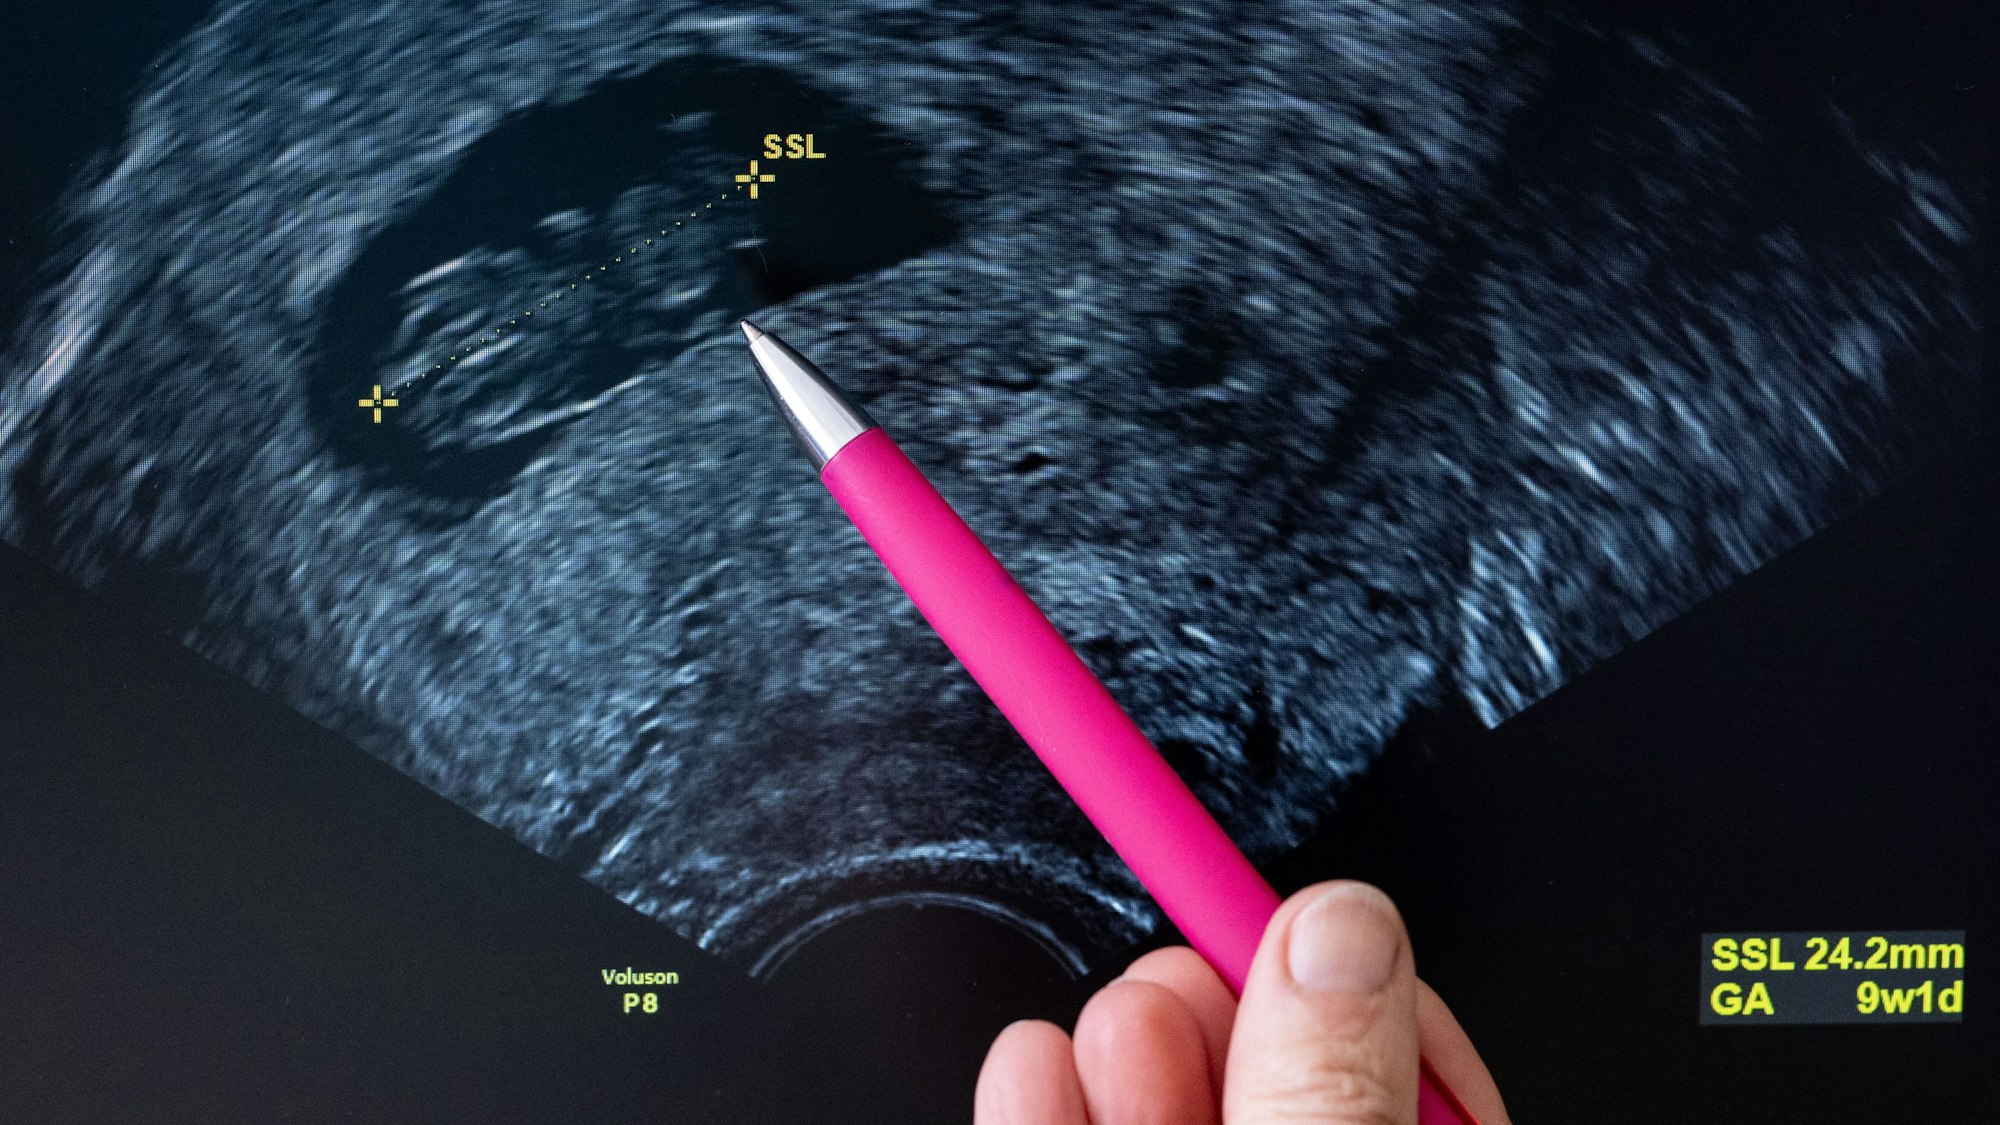

Eine Frauenärztin deutet auf den Kopf eines Fötus im Ultraschall. (Symbolbild)

Schwangere erhalten in Deutschland einer Barmer-Analyse zufolge zu viele Untersuchungen ohne medizinischen Grund. Abrechnungsdaten zeigen bei Ultraschall- und CTG-Untersuchungen eine Überversorgung, wie eine der Nachrichtenagentur AFP am Mittwoch vorliegende Untersuchung des Barmer-Instituts für Gesundheitssystemforschung nahelegt. Die Versorgung übersteige die Vorgaben der Mutterschaftsrichtlinie.

Diese sieht vor, dass gesunde Frauen mit unauffälliger Schwangerschaft drei Ultraschalluntersuchungen erhalten. Zusätzliche Ultraschalluntersuchungen soll es nur geben, wenn ein konkretes Risiko besonders überwacht werden muss. CTG-Aufnahmen, mit denen Herztöne des Kindes und Wehen der Mutter aufgezeichnet werden, werden nur bei klaren medizinischen Indikationen empfohlen.

Der Analyse zufolge erhalten jedoch gesunde Frauen in etwa genauso viele Untersuchungen wie Schwangere mit medizinischen Risikofaktoren wie zum Beispiel Diabetes oder vorangegangenen Früh- oder Fehlgeburten. Mehr als die Hälfte wurden fünf bis neun Mal mit Ultraschall und CTG untersucht. Nur rund ein Drittel (34,4 Prozent) der Frauen ohne Risiken erhielten wie vorgesehen bis zu drei Ultraschalluntersuchungen.

4,7 Prozent der gesunden Schwangeren bekommen sogar zwischen zehn und 14 dieser Untersuchungen. Obwohl nicht empfohlen, wurden demnach gesunde Frauen mit unauffälliger Schwangerschaft im Schnitt fünf Mal mit CTG kontrolliert.